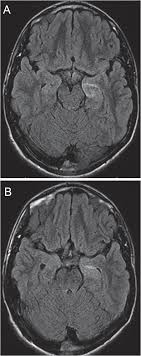

Babies with cancer can have many different symptoms, depending on what type of cancer it is. Therefore, as brain tumors develop and expand, they cause extra pressure in this closed space. Environmental causes of brain cancer in children spring 2003. Approximately 2,200 children in the us are diagnosed with a brain tumor each year. Increased intracranial pressure is caused by extra tissue in the brain as well as blockage of the cerebrospinal fluid flow pathways.

But certain types of brain tumors, such as medulloblastoma or ependymoma, are more common in children. As the tumor grows, it creates pressure on and changes the function of surrounding brain tissue, which causes signs and symptoms such as headaches, nausea and balance problems. Environmental causes of brain cancer in children spring 2003. Problems speaking clearly, swallowing, or walking. In children, tumors usually start in a part of the brain that controls movement and coordination. Because these bones are still malleable, a brain tumor could cause their head to grow in abnormal ways. What are the signs of cancer in babies? Most often, it's not known why children without inherited syndromes develop brain or spinal cord tumors. A tumor is an abnormal growth of tissue. A brain tumour is a collection of cells that have grown in an uncontrolled way. Can brain and spinal cord tumors in children be prevented? Brain and nervous system cancers; Tumors can occur at any age.

When babies are young, their skull bones haven't fused (or grown together) yet. This is called intracranial pressure. Increased intracranial pressure is caused by extra tissue in the brain as well as blockage of the cerebrospinal fluid flow pathways. Brain tumors are the most common solid tumors in children. Tumors can occur at any age.

In children, tumors usually start in a part of the brain that controls movement and coordination. As the tumor grows, it creates pressure on and changes the function of surrounding brain tissue, which causes signs and symptoms such as headaches, nausea and balance problems. Your child may have any of the following: Areas that are weak or numb in an arm or leg, or loss of balance. Though uncommon, a family history of brain tumors or a family history of genetic syndromes may increase the risk of brain tumors in some children. A brain tumor can form in the brain cells (as shown), or it can begin elsewhere and spread to the brain. Environmental causes of brain cancer in children spring 2003. Brain tumors and other nervous system tumors make up about 27 percent of childhood cancers. When brain cells grow abnormally or out of control, a tumor (a mass of cells) can form. The cause of most childhood brain tumors is unknown. Known risk factors for brain cancer include: More children than ever are surviving childhood cancer. Boys are affected slightly more often than girls.